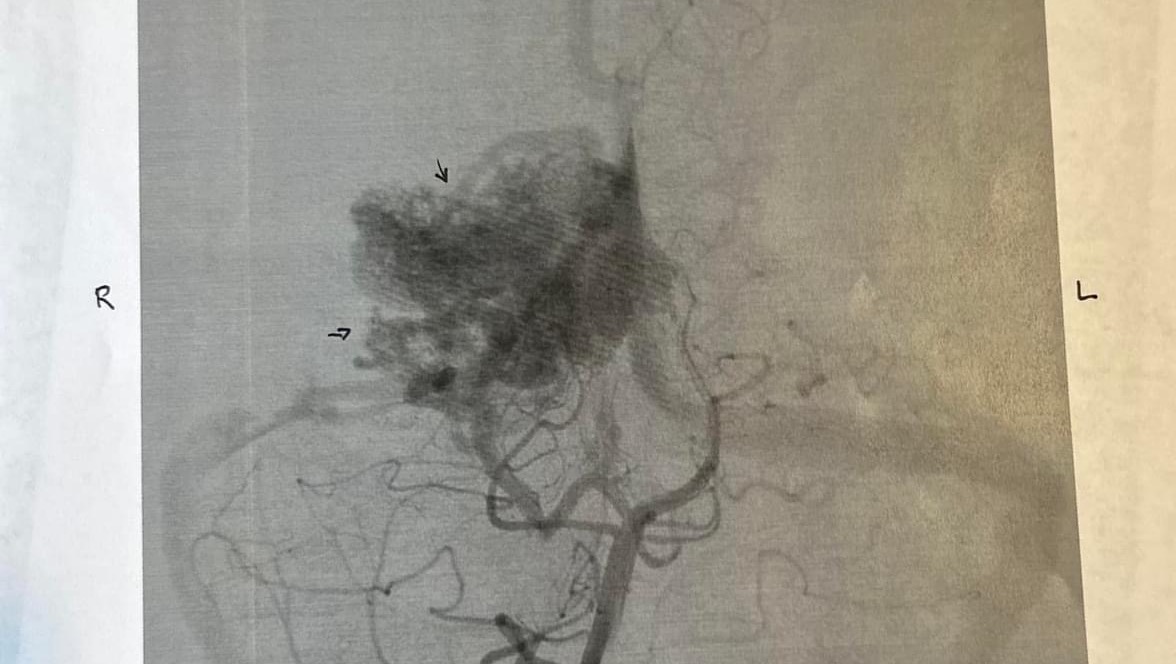

Early in December, she began complaining of a severe headache. Headaches are nothing new for Kenzie. She has had intermittent migraines with “visual auras”over the last several years. But after 9 days of failed outpatient treatment, we headed to the ER, where an MRI revealed a large (grade 4) Occipital AVM.

AVMs or Arteriosclerosis-Venous Malformations are an area of blood vessels that, instead of forming in straight lines, form in a bundle (or, as Kenzie likes to say, a knot). Instead of having clear high-pressure tolerant arteries and low pressure venous drainage, these vessels are mismatched and hopelessly tangled. Because of this malformation, there is also no capillary bed within her “knot” to allow oxygen and nutrient to exchange. AVMs are the leading cause of stroke in the pediatric population and are often not discovered unless one of those vessels ruptures and bleeds.

We were quickly transferred to OHSU and placed in the amazing care of their neurosurgical team for ongoing testing. This included a brain angiogram and that showed her AVM was larger than originally thought, measuring about 5cm x 3cm. During that hospitalization, it was discovered that her AVM has already started to cause her permanent side effects. She has lost a good portion of her left upper field of vision in both eyes.